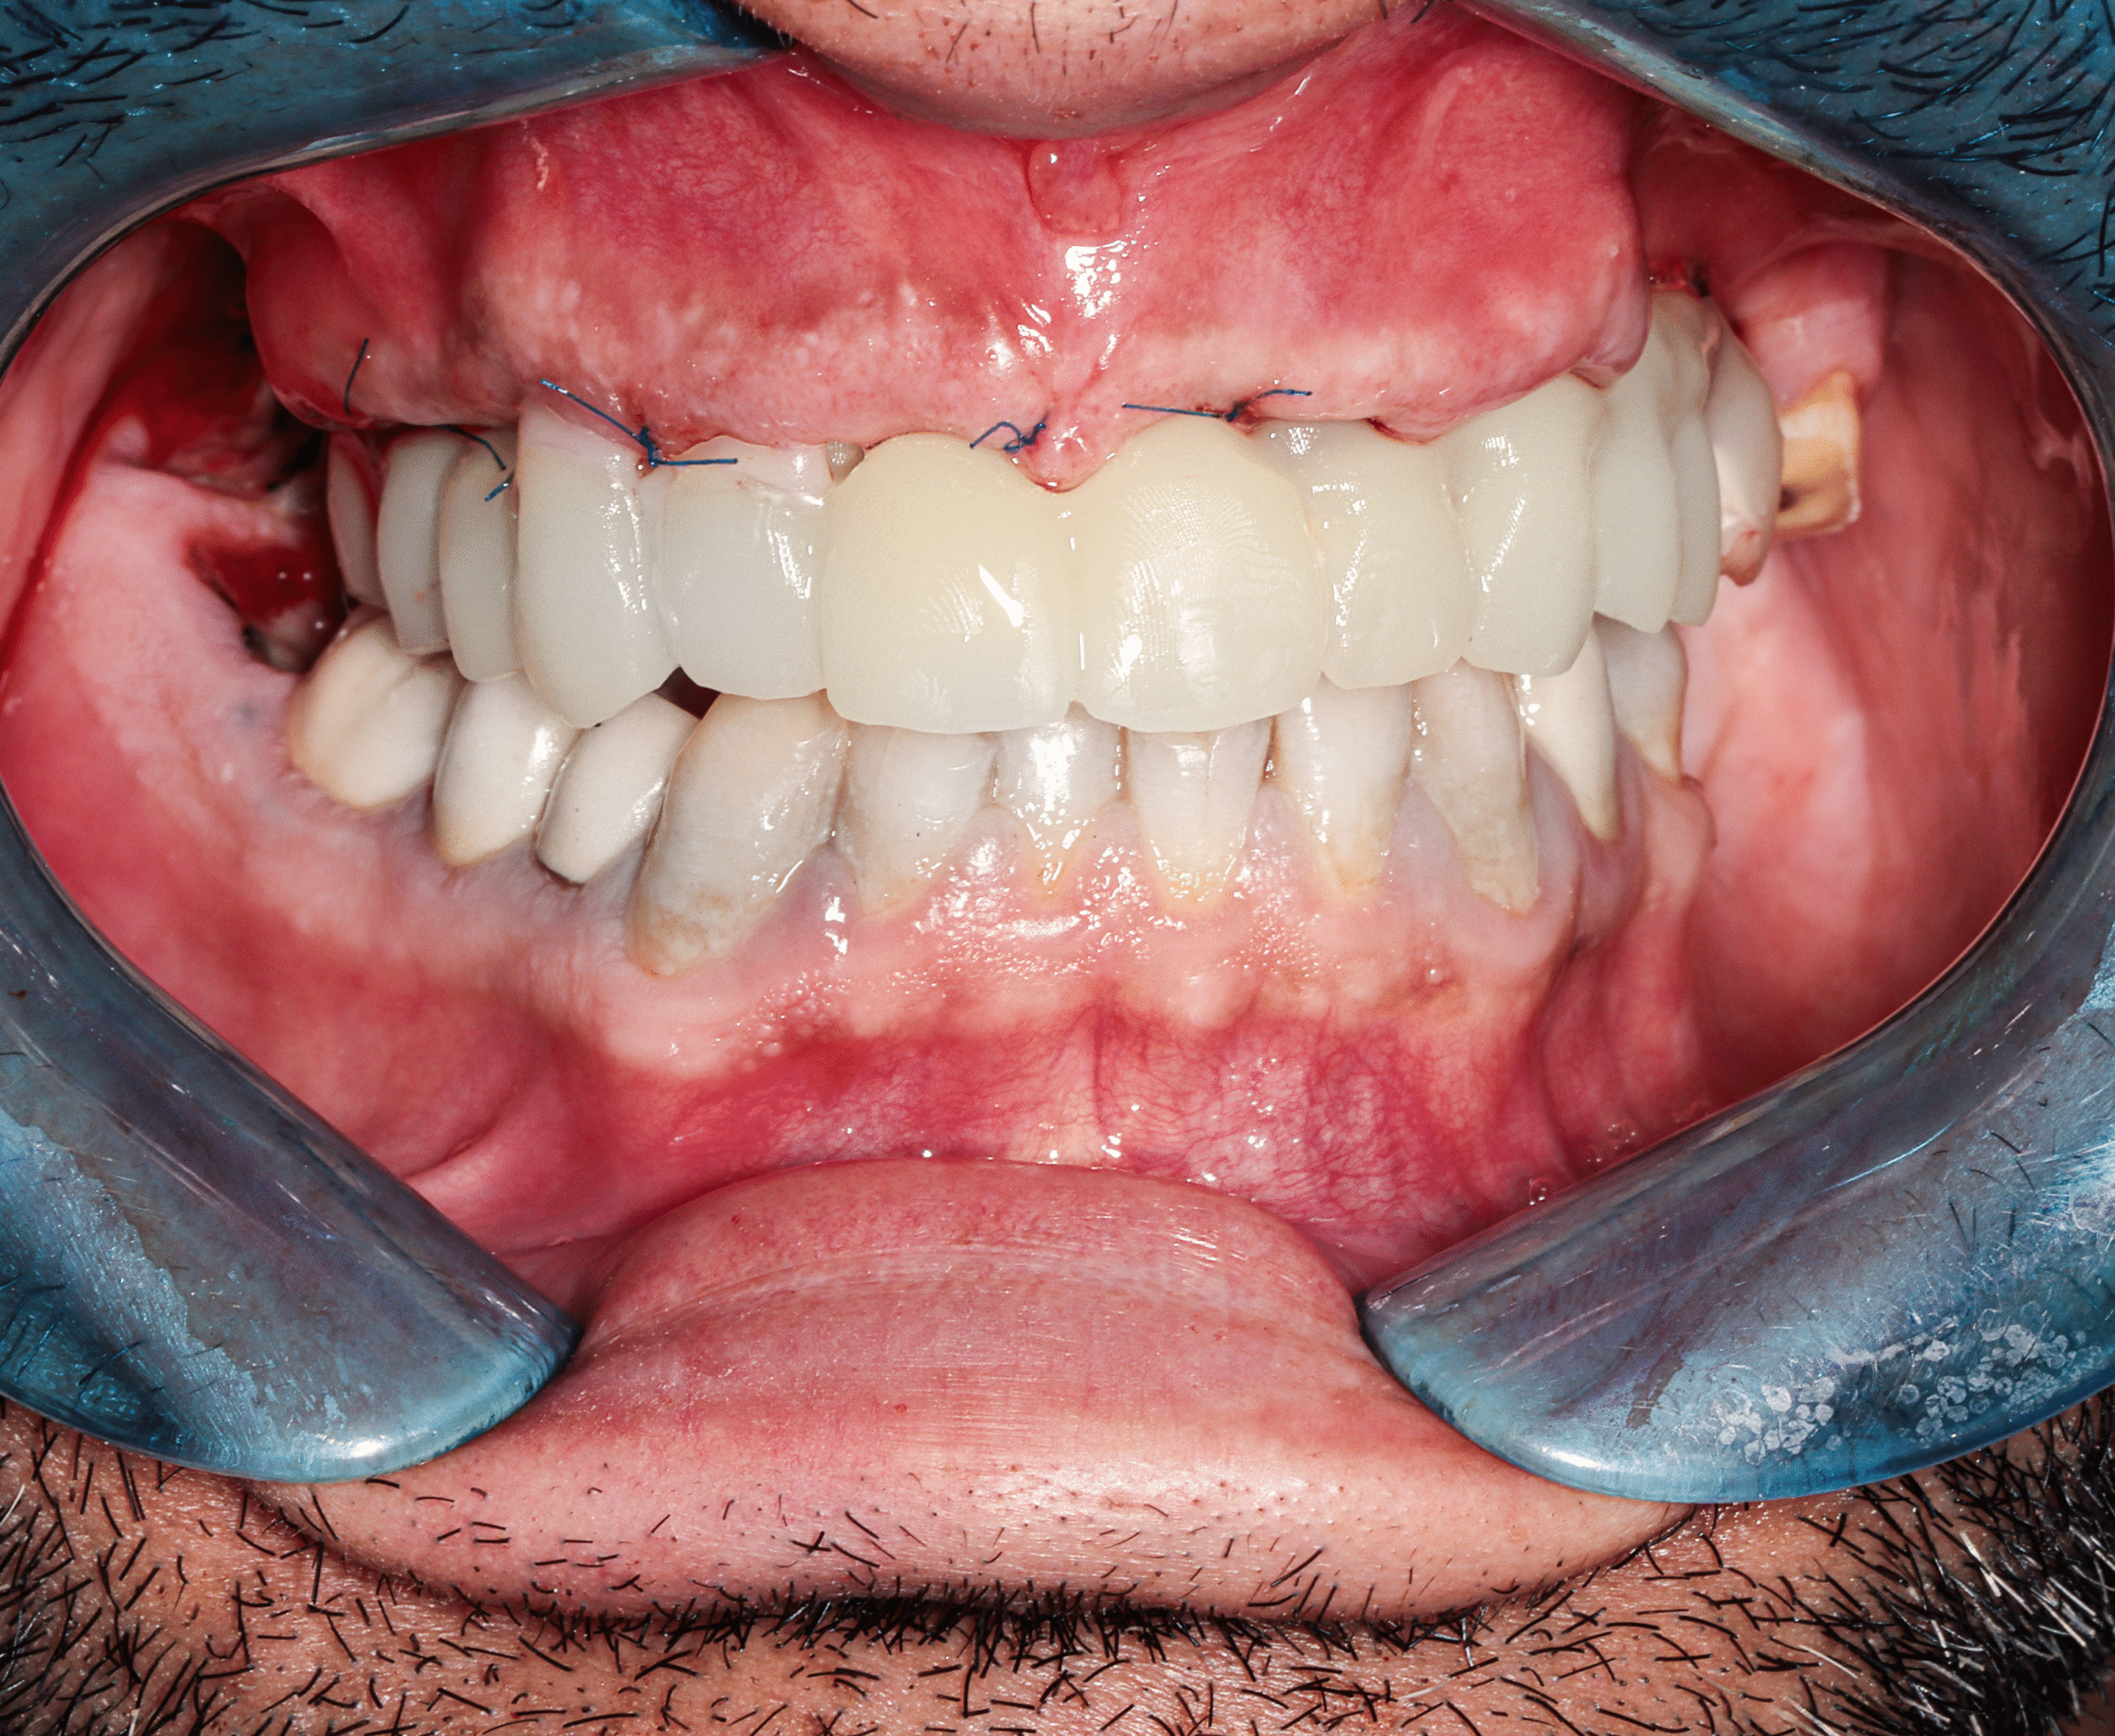

After

Step 4 — Immediate Temporary Restoration

- Same-day delivery of a full set of temporary fixed teeth

- Instant improvement in Jonathan’s smile, speech, chewing function, and facial proportions

Step 5 — Final Prosthesis After Healing